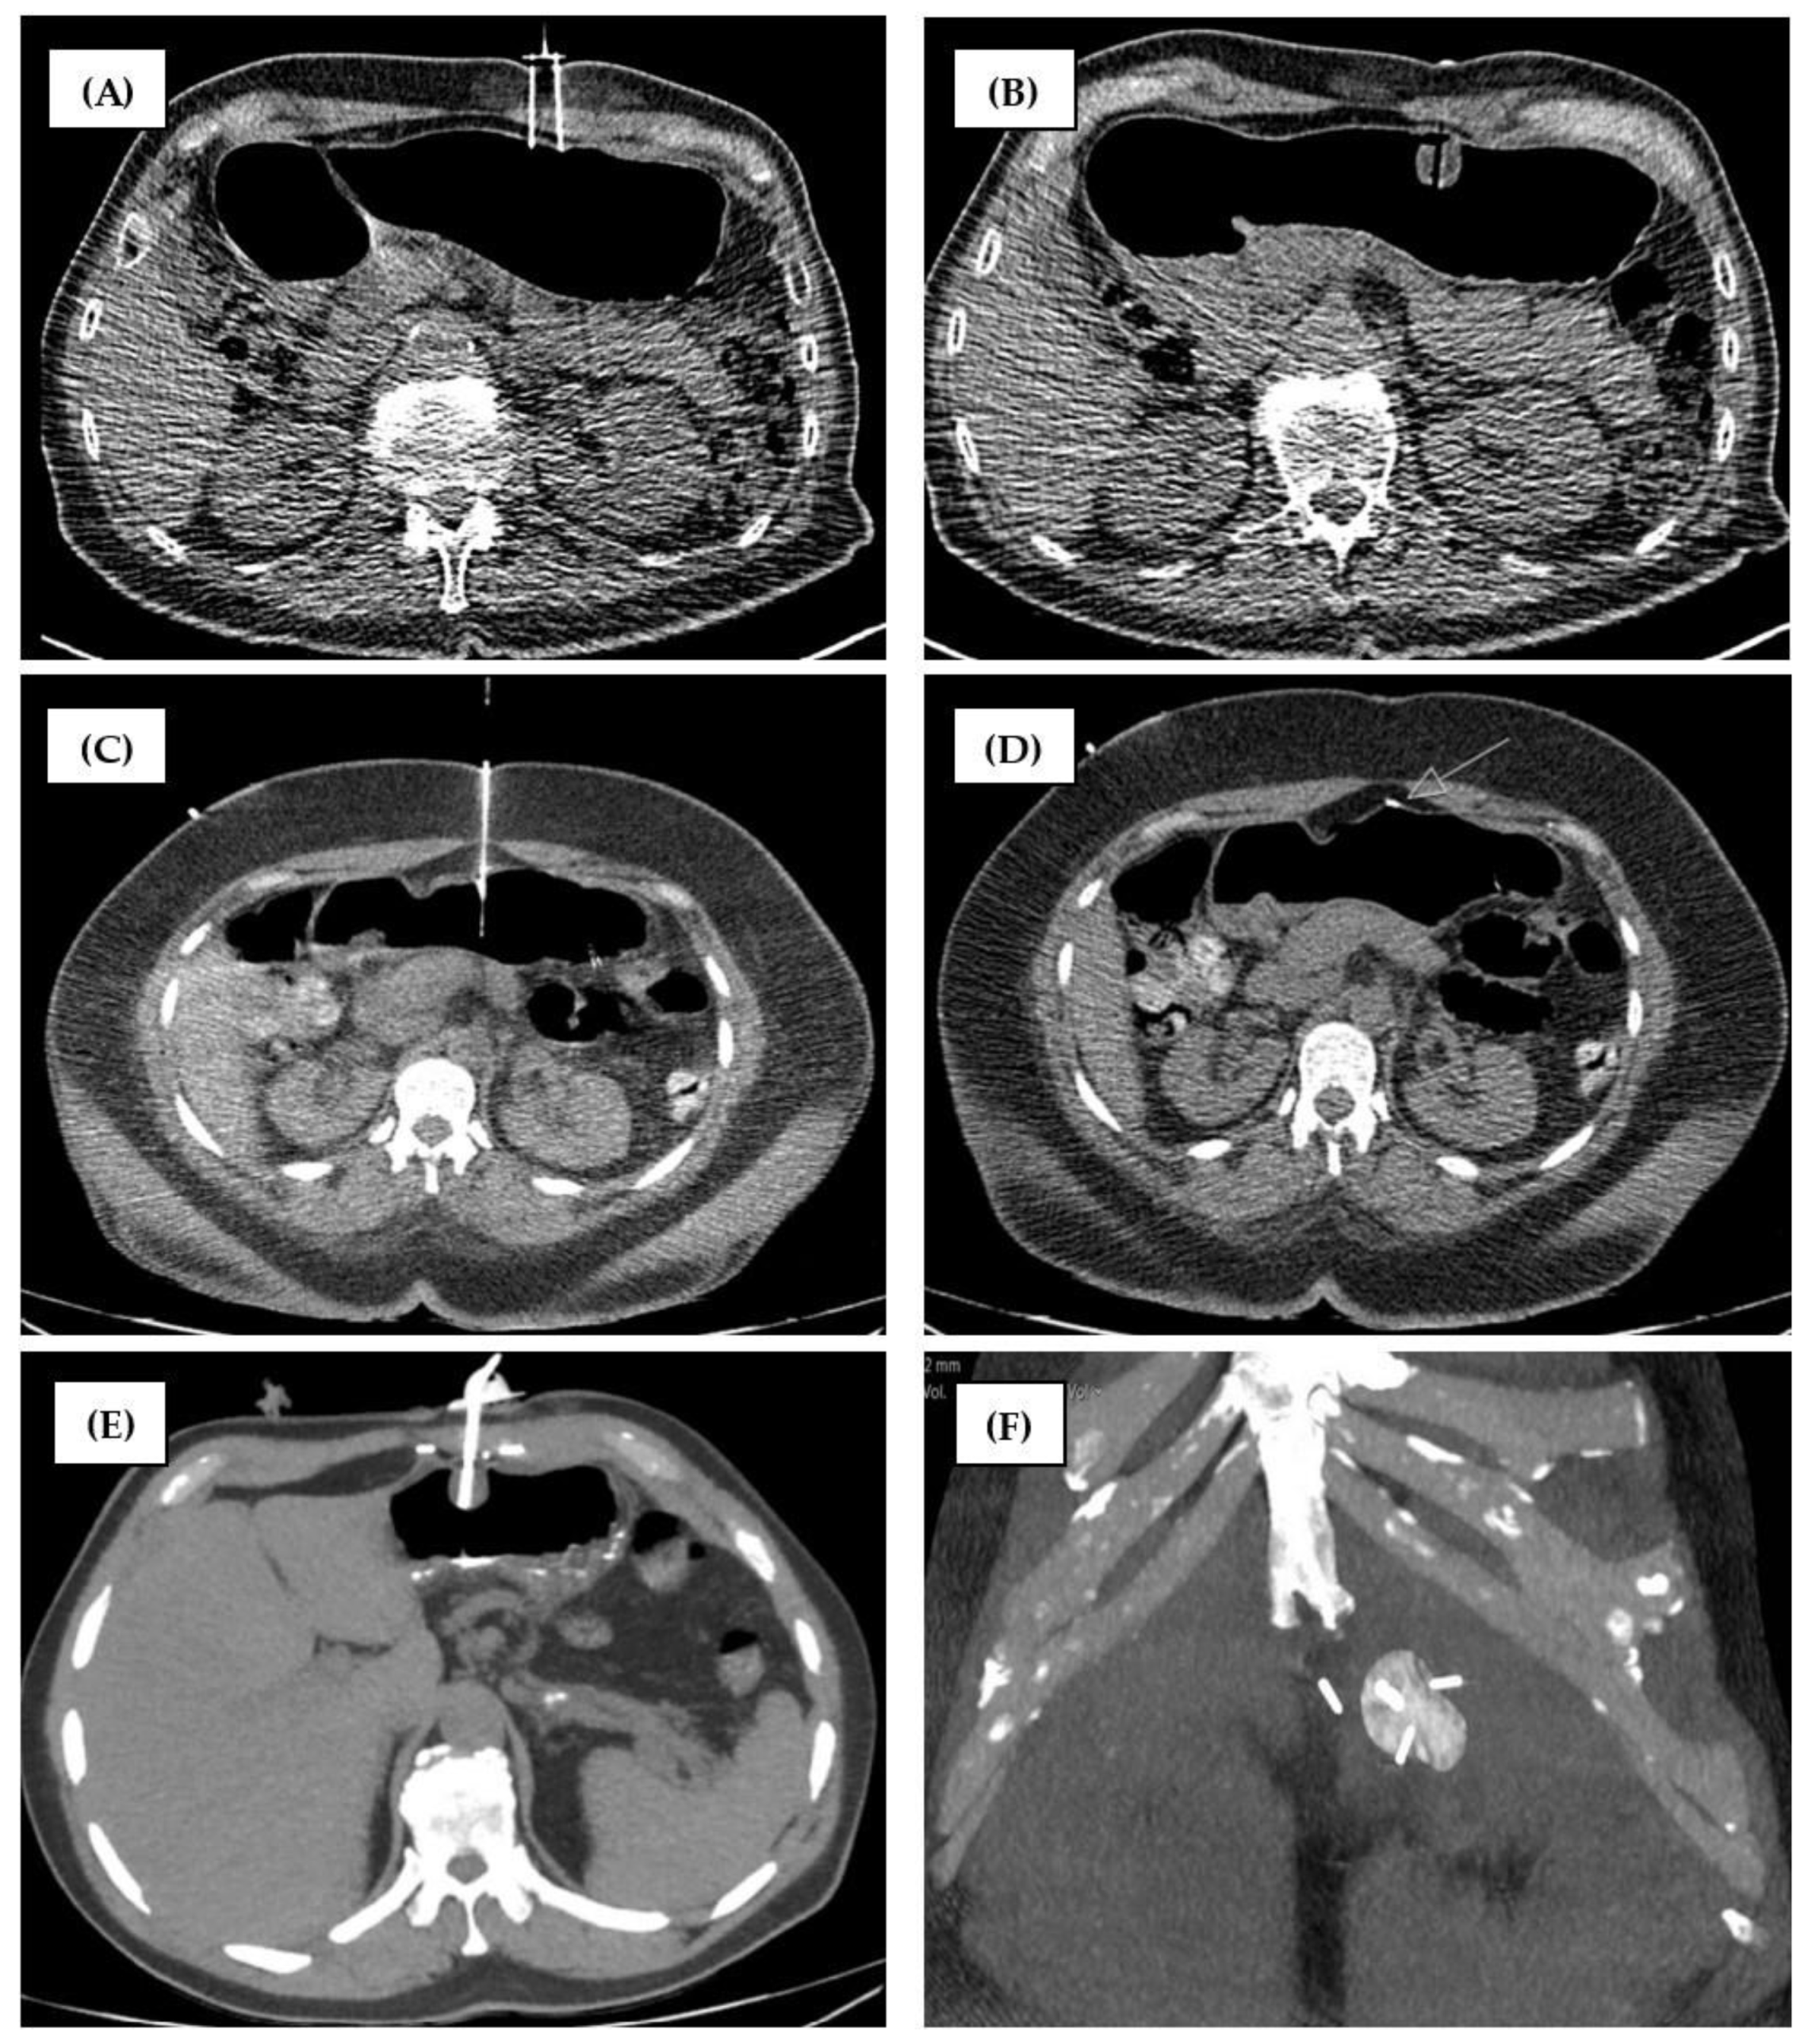

2.2. CT-Guided PRG Techniques at the Two Study Sites

2.2.1. Group 1 (MS-CT BM and Retention Anchor Suture)

2.2.2. Group 2 (RT-CTF and Gastropexy Device)